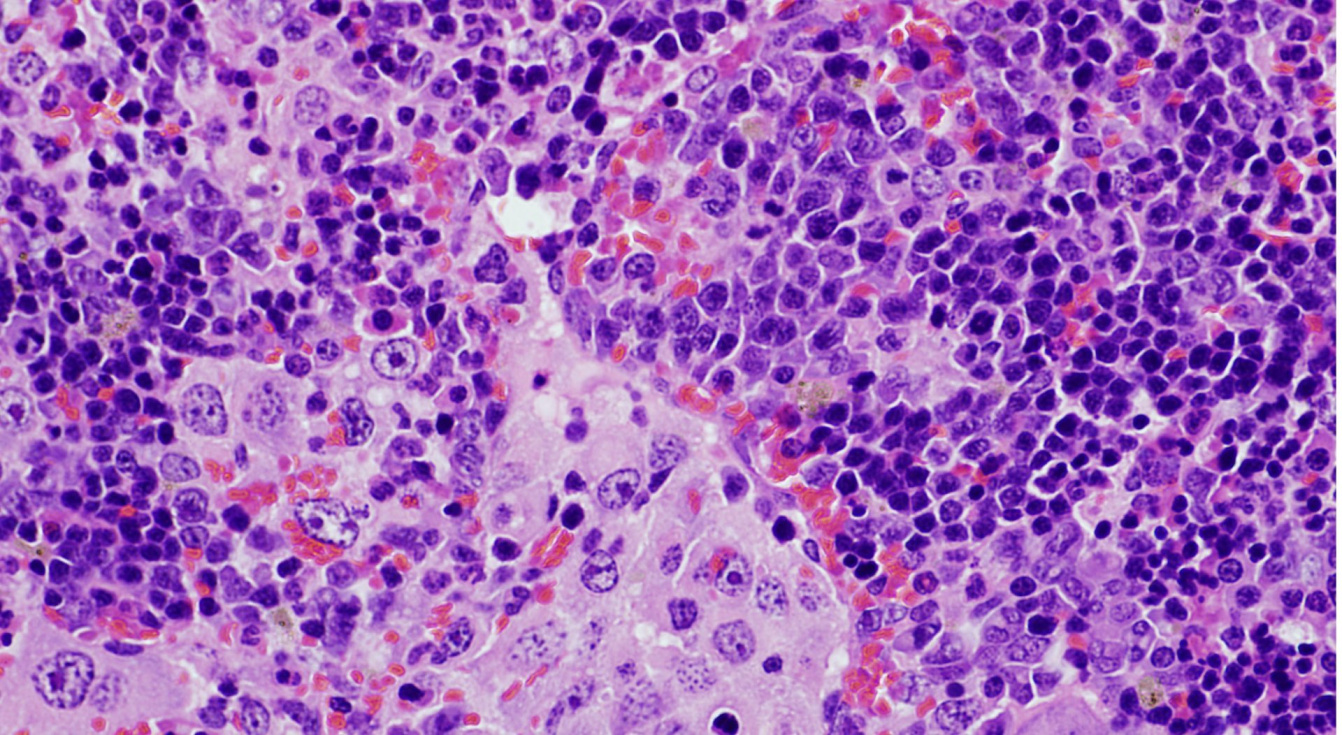

El trabajo muestra que el espectro de tumores generados depende de la presencia de alteraciones genéticas en otros dos genes distintos (TRP53 y KRAS). A partir de un modelo de ratón modificado genéticamente que contenía la alteración en el gen VAV1, los investigadores han podido determinar el papel de este gen en varios tipos de cáncer. “Por un lado, hemos demostrado que la alteración genética en VAV1 no es suficiente para inducir la formación de tumores en ningún órgano de los ratones. Sin embargo, cuando se combina con la eliminación del gen antitumoral TRP53 provoca el rápido desarrollo de un tumor muy específico de linfocitos T conocido con el nombre de linfoma periférico de células T. Pero no se han detectado otros tipos tumorales, indicando que la combinación de estas dos alteraciones genéticas solo da lugar a un tipo de tumor”, señala Robles-Valero.

“El gen VAV1 se detectaba en tumores derivados de células que, como los linfocitos T (responsables de nuestras respuestas inmunes), sí expresaban de forma normal este gen. Sin embargo, también se detectaba en algunos tumores que, como en el cáncer de pulmón, derivaban de células que normalmente no expresaban esta proteína. Esto nos hizo preguntarnos si esta alteración genética era importante en ambos casos y, en dicho caso, intentar conocer los mecanismos que influencian el desarrollo de estos tumores”, apunta Javier Robles-Valero, científico del CIC (CSIC-USAL) y el Centro de Investigación Biomédica en Red (CIBERONC) y primer autor de este trabajo.